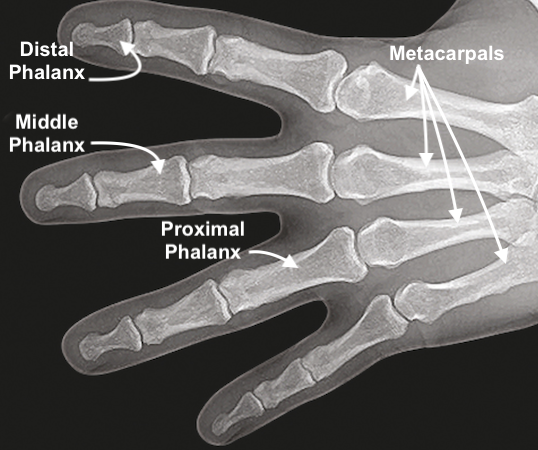

Next evaluate the bones of the finger for tenderness that is not related to the laceration alone. This can be done by gently palpating the bones of the finger. To palpate for bony tenderness the examiner should palpate the distal phalanx, middle phalanx, and proximal phalanx of the finger by applying pressure to the bone without simultaneously palpating the laceration. With an extensive laceration this may not be possible. With severe lacerations the increased pain caused by even gentle palpation of the skeletal structures may make palpation of the bones impossible.

• Bones of the fingers.